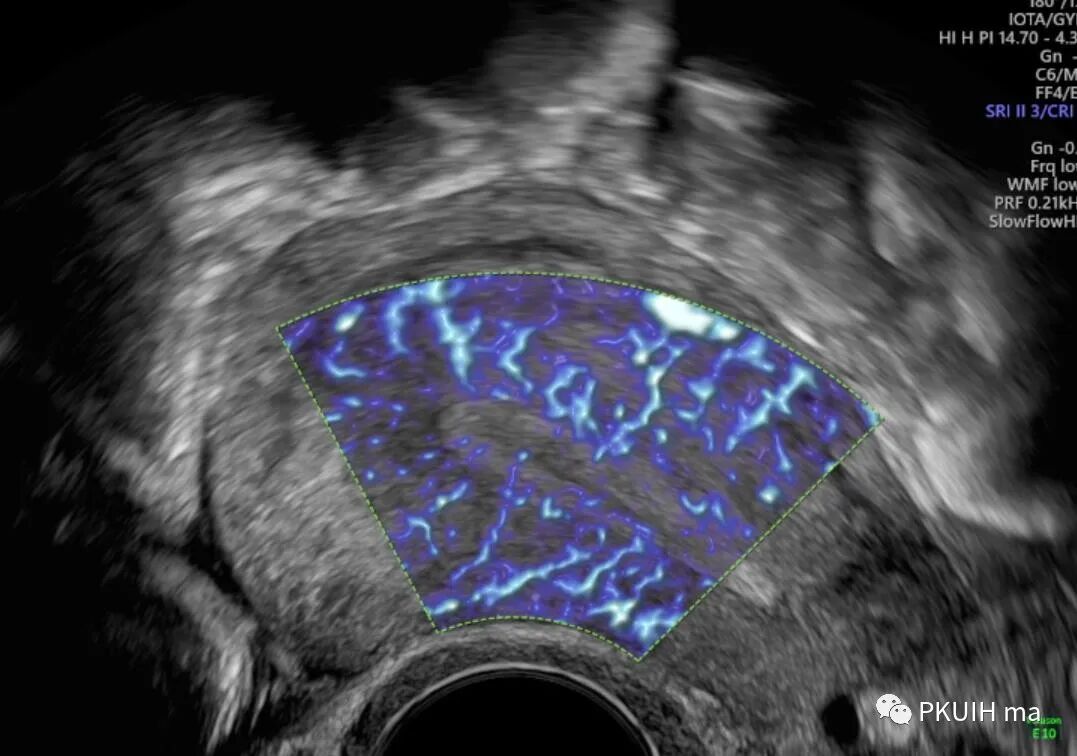

GE的SlowFlow功能还是有作用的。看看下面这几张,第一第二张图用CD和HD都不能完美的显示胎儿大脑Willis环,采用SlowFlow功能能够显示完整的颅底动脉环

通过这个血流成像前交通后交通都能完美显示